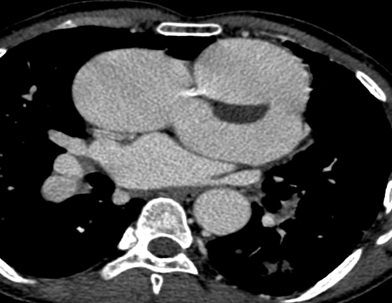

Persistent truncus arteriosus is an uncommon complex congenital heart disease. Without surgical intervention, the prognosis is not good. Very few untreated cases of truncus arteriosus survive to maturity. We report an exceptional case of uncorrected truncus arteriosus surviving into adulthood of type a3 variant -van praagh classification as a 26-year-old male who had well tolerated dyspnea since birth. Our patient showed a single(right) pulmonary artery arising from the common arterial trunk supplying the right lung and absent main and left pulmonary artery with collateral supply to the left lung consistent with the truncus arteriosus type a3-van praagh classification